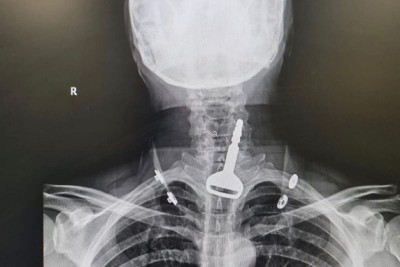

إنقاذ حياة «أربعيني» ابتلع مفتاح سيارته

نجح فريق طبي بمدينة القنفذة، في استخراج مفتاح سيارة عالق بالجهاز التنفسي لمريض أربعيني، كاد أن يودي بحياته، في عملية سريعة استغرقت 15 دقيقة عن طريق المنظار. وأكدت وزارة الصحة أن الفرق الطبية تمكنت من إنقاذ حياة مريض يبلغ من العمر 49 عاما وصل لقسم الطوارئ وهو يعاني من انسداد بمجرى التنفس، حيث اتضح بعد إجراء الفحص السريري والأشعة وجود مفتاح سيارة عالق في القصبة الهوائية. وأوضحت أن المريض الذي اعترف للأطباء... |